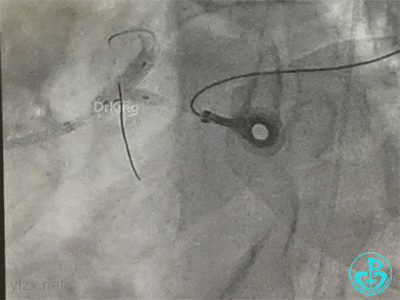

冠脉造影

右冠脉近中段不规则狭窄。短左主干中度狭窄,前降支开口严重狭窄,多功能造影导管推注造影剂时无反流,导管退出左主干开口造影发现左主干狭窄严重。

治疗过程

患者血压持续偏低,加快输液速度,IABP预备,去甲肾上腺素微量泵静脉输注提高血压。